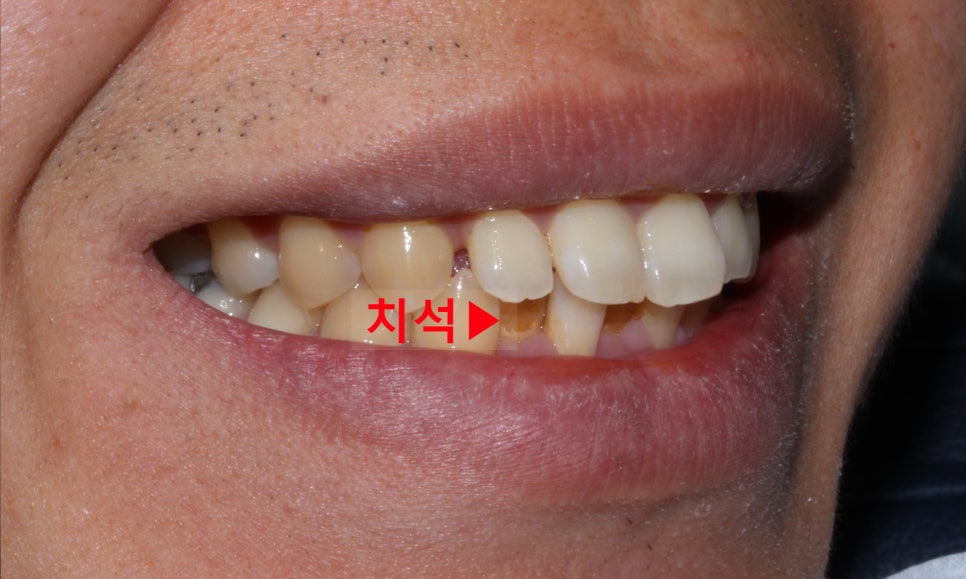

'뻐드렁니 교정 전(Before)'

뻐드렁니 부분교정 전

2D치과(투디치과)

뻐드렁니 교정 전 입술을 보시면

앞니의 돌출감으로 인해 입술이

튀어나와 있는 모습인데요,

앞니가 입술 방향으로 뻐드러져 있어

아랫니가 윗니에 많이 가려져 있는 모습입니다.

(+과개교합 증상이 보이는 모습이에요)

아랫니의 경우에는 삐뚤삐뚤한 치열로 인해

치아 사이에 치석이 많이 끼어있고 지저분한 모습입니다ㅠ0ㅠ

이렇게 치아에 총생(삐뚤거림)이 있는 경우

가지런한 치열보다 치아를 깨끗하게 관리하기 어렵고

칫솔이 닿지 않는 부분에 치석이 쌓일 가능성이 높습니다!